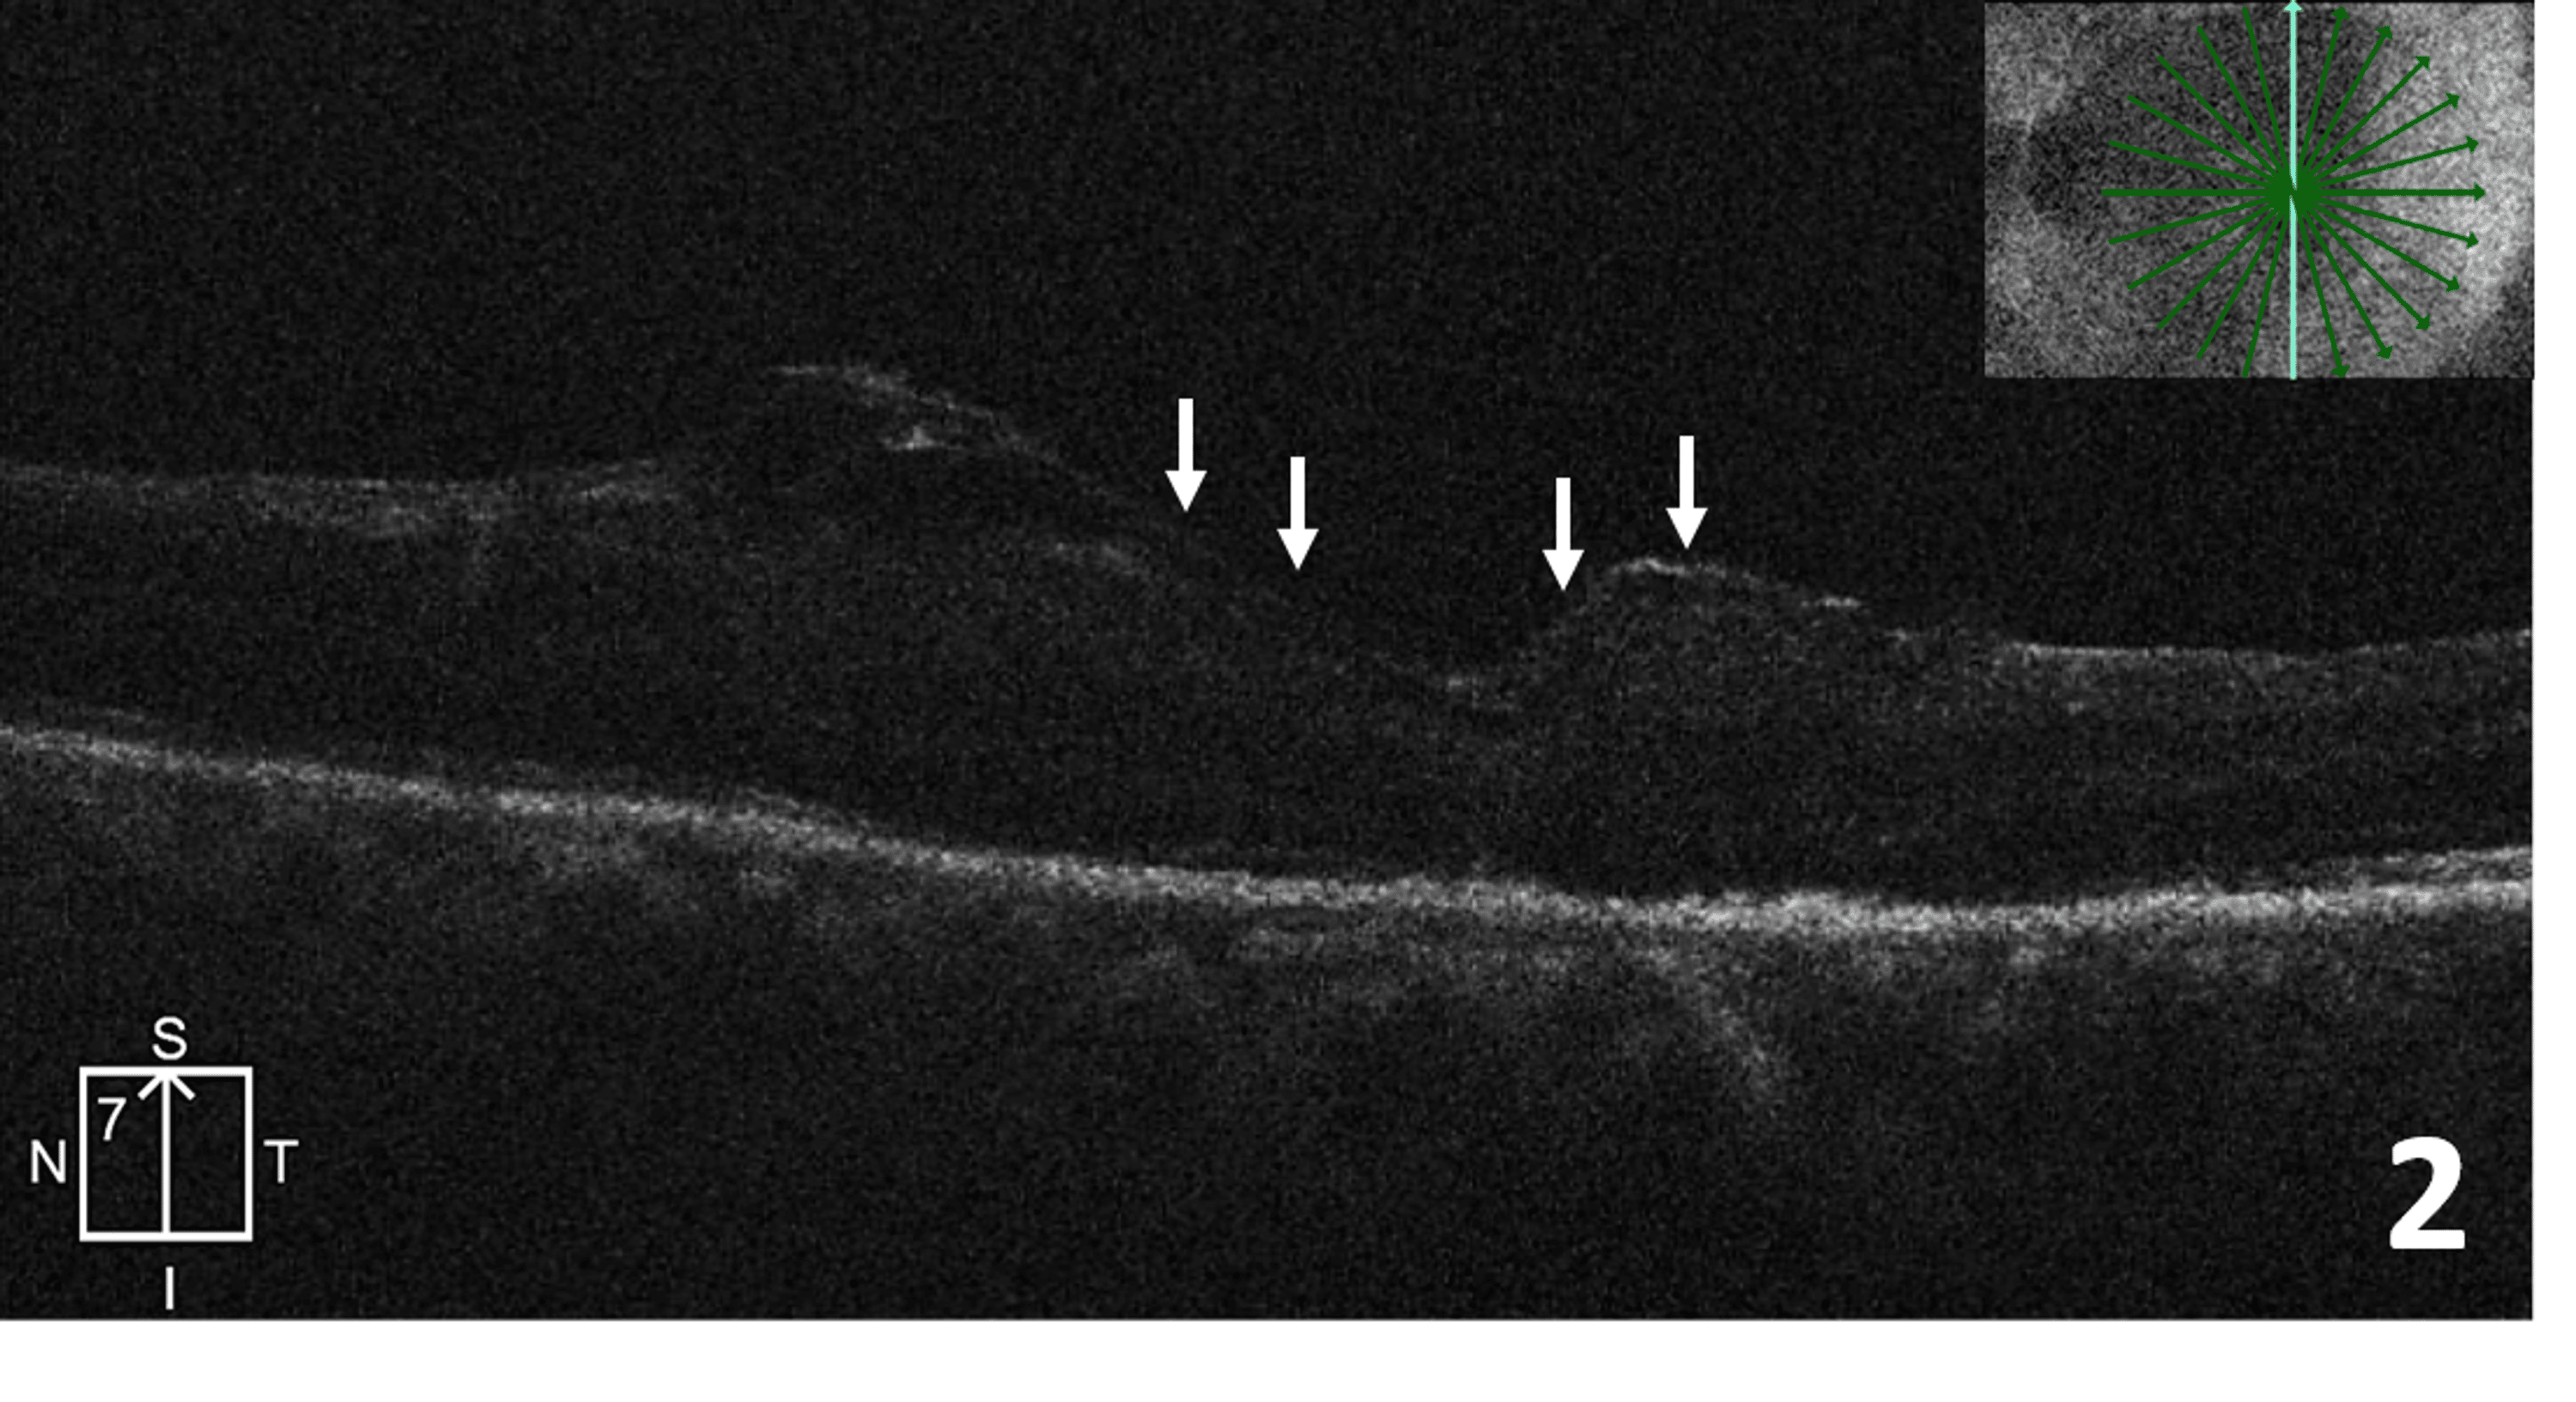

Macular hole closure over time after posterior lens capsular flap Lens Capsular Flap Lens capsular flap is effective in sealing posterior retinal holes and treating the associated retinal detachment without the complication resulting. In terms of visual recovery, the most efficient technique for treating refractory ftmh is ham, lens capsular flap and apc that. To report the comparison of the therapeutic effects of lens capsular flap transplantation (lct) and autologous retinal. Lens capsular. Lens Capsular Flap.

A macular hole closed surgically with a lens capsular flap. Download Lens Capsular Flap To report the clinical results of lens capsular flap transplantation in refractory macular hole (mh). Lens capsular flap is effective in sealing posterior retinal holes and treating the associated retinal detachment without the complication resulting. To report the comparison of the therapeutic effects of lens capsular flap transplantation (lct) and autologous retinal. Lens capsular flap is effective in sealing posterior. Lens Capsular Flap.

Example of lens capsular flap in treatment of retinal detachment due to Lens Capsular Flap To report the clinical results of lens capsular flap transplantation in refractory macular hole (mh). Lens capsular flap is effective in sealing posterior retinal holes and treating the associated retinal detachment without the complication resulting. Lens capsular flap is effective in sealing posterior retinal holes and treating the associated retinal detachment without the complication resulting. To report the comparison of. Lens Capsular Flap.

Macular hole closure over time after posterior lens capsular flap Lens Capsular Flap Lens capsular flap transplantation may help to improve the closure rate and visual outcomes in large mhs, which could be an alternative method as primary treatment for large mhs. To report the comparison of the therapeutic effects of lens capsular flap transplantation (lct) and autologous retinal. Lens capsular flap is effective in sealing posterior retinal holes and treating the. In. Lens Capsular Flap.